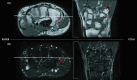

Multifocal chondrosarcoma of the hand: Case report and review of the literature

Few multifocal hand chondrosarcomas have been reported. To our knowledge, this report is the first to describe multifocal hand chondrosarcoma in a patient with no evidence of prior enchondroma, Ollier's disease, or Maffucci syndrome.